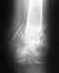

Спасибо, Др Гофман, что проконсультировали, посмотрите, пожалуйста, мои снимки за третье декабря. Повторно мне снимки не назначают, даже не говорят, как долго можно ходить в день и какие нужно делать упражнения. Передвигаюсь по дому на костылях и в жёстком сьёмном корсете.

Этих снимков недостаточно что бы определить тяжесть вашего состряния

Нужны снимки сагиттальные (срединный разрез по длине тела) и обязательно новые снимки (хотя бы обычные рентгеновские, не КТ, но новые ) для поясничного и грудного отдела и без корсета и стоя.

Сегодня продливали больничный лист у доктора и снимки не назначают. Прикрепляю файл со всеми ранними снимками КТ.Заранее спасибо.

Грудной кифоз выпрямлен. Тело Th11 позвонка деформировано, неравномерно снижено по высоте, определяется оскольчатый перелом тела Th11 позвонка справа и в передних отделах, слева высота тела сечением в задних отделах до 22 мм, в передних отделах до 12 мм, справа мах осколок сечением до 28 на 14 мм, который в задних отделах тесно прилежит к правому реберно-позвоночному сочленению в его каудальных отделах, не деформируя его. На уровне Th11-12 имеется угловая деформация позвоночника до 159 градусов. Межпозвонковый диск на уровне Th11-12 неравномерно снижен по высоте, мах в передних отделах слева.

Высота тел других позвонков на уровне исследования сохранена. Тела других позвонков имеют обычную форму и размеры, костная структура не изменена. Замыкательные пластинки уплотнены. Имеются неравномерные сужения суставных щелей, субхондральный склероз, краевые сотеофиты. Кальцинированы жёлтые связки.

Существенных выпячиваний дисков не выявлено. Область невральных каналов без особенностей.

Сагиттальный размер позвоночного канала на уровне Th1-12-13-14 мм, на других уровнях 13.5-15 мм.